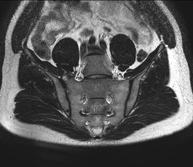

- RM Sacroilíacas

Prueba diagnóstica no invasiva que consiste en la obtención de imágenes de alta definición anatómica de las articulaciones sacroilíacas mediante el empleo de un campo electromagnético y ondas de radio (con un emisor y un receptor). No utiliza radiación ionizante. Indicaciones: dolor sacroilíaco inflamatorio.

Estudio específicamente diseñado para valorar estas articulaciones y su inflamación en los pacientes que sufren Espondilitis Anquilosante. También resulta de utilidad en pacientes con traumatismos y posibles fracturas del sacro y el cóccix. Tiene una duración aproximada de 16 minutos. No emplea radiación ionizante.